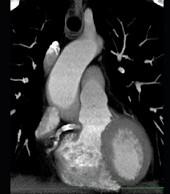

下面一组图像应考虑为 ( )A、左前降支钙化B、左旋支钙化C、正常的左前降支D、右侧冠状动脉钙化E、正常的右侧冠状动脉

问题 下面一组图像应考虑为 ( )

选项 A、左前降支钙化 B、左旋支钙化 C、正常的左前降支 D、右侧冠状动脉钙化 E、正常的右侧冠状动脉

答案 D